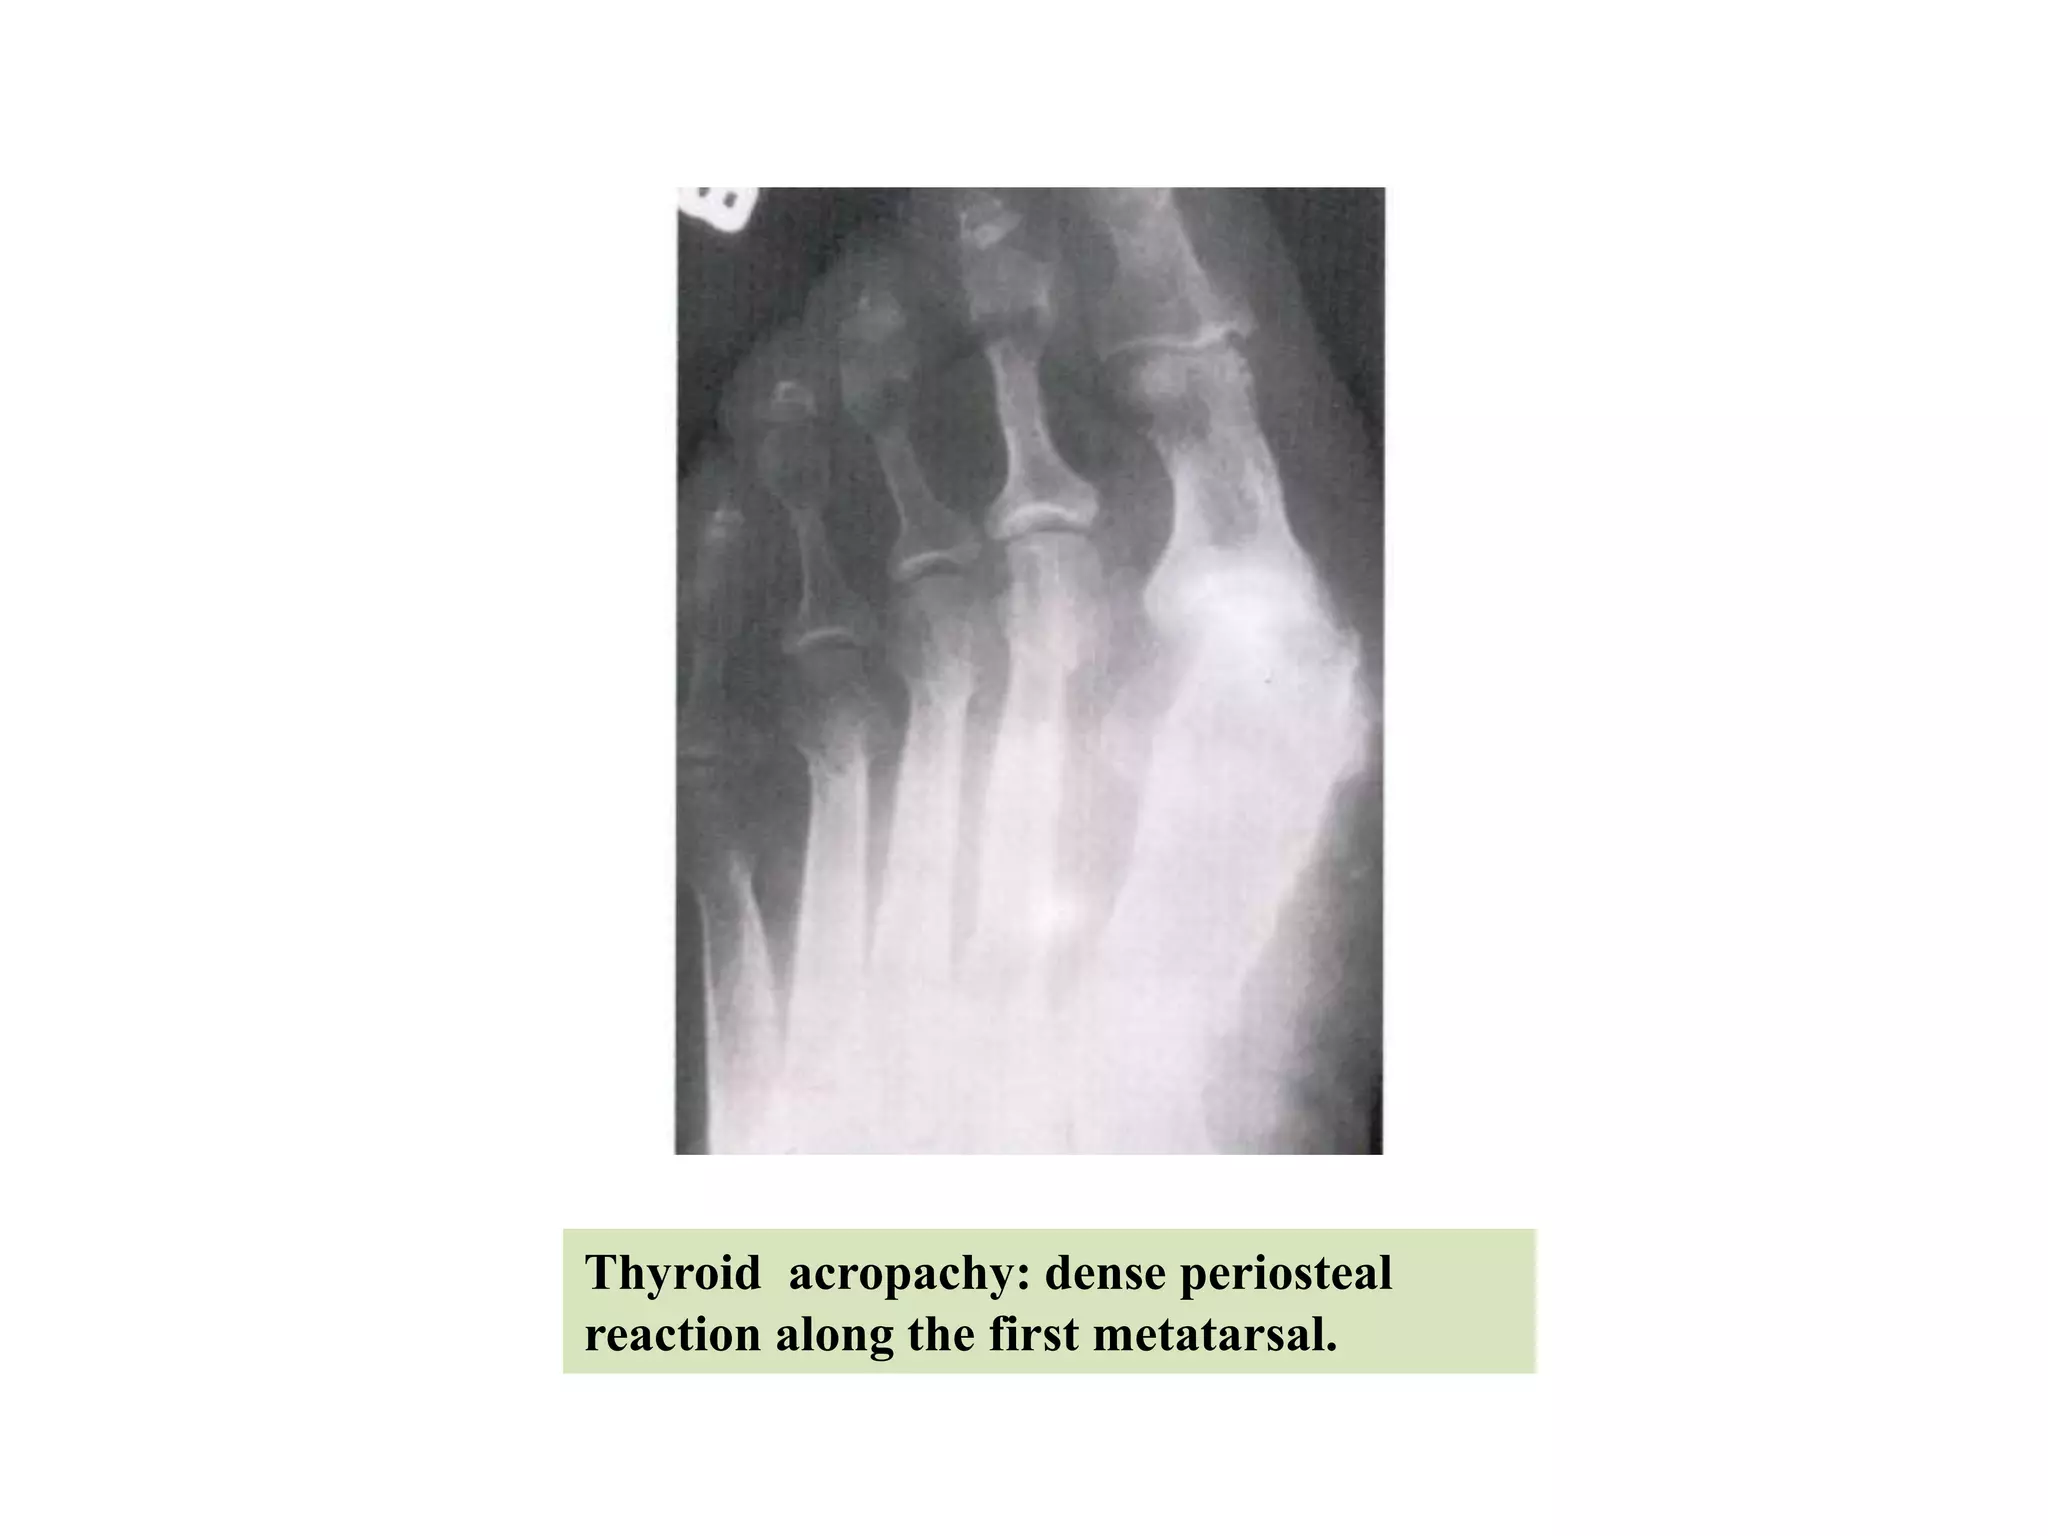

Thyroid acropachy

•It is a triad of pre-tibial myxoedema, exophthalmos &

clubbing of the fingers.

• Radiologically there is characteristic periosteal

thickening in the extremities; commonest &

characteristic site of involvement is the first metacarpal

or metatarsal.

Thyroid acropachy: dense periosteal

reaction along the first metatarsal.